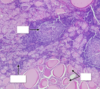

Medullary Thyroid Carcinoma